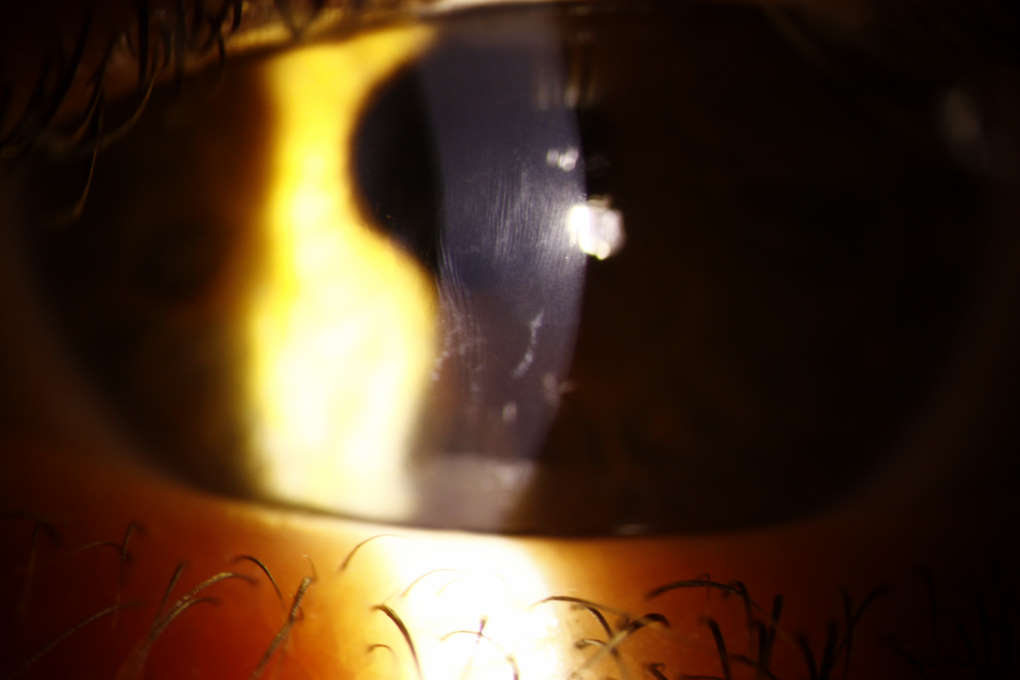

Keratoconus

Prevalence estimates for keratoconus in DS range from 0.5-30%. The corneas of individuals with DS are inherently steeper, thinner and biomechanically weaker than non-DS counterparts. Given the clinical predisposition for keratoconus, it is conceivable that there may be a genetic link between keratoconus and chromosome 21. Others have attributed keratoconus in this group to mechanical trauma from eye rubbing, however, evidence for this is yet to be fully established.

Vogt’s striae and anterior stromal scarring in an individual with DS and keratoconus